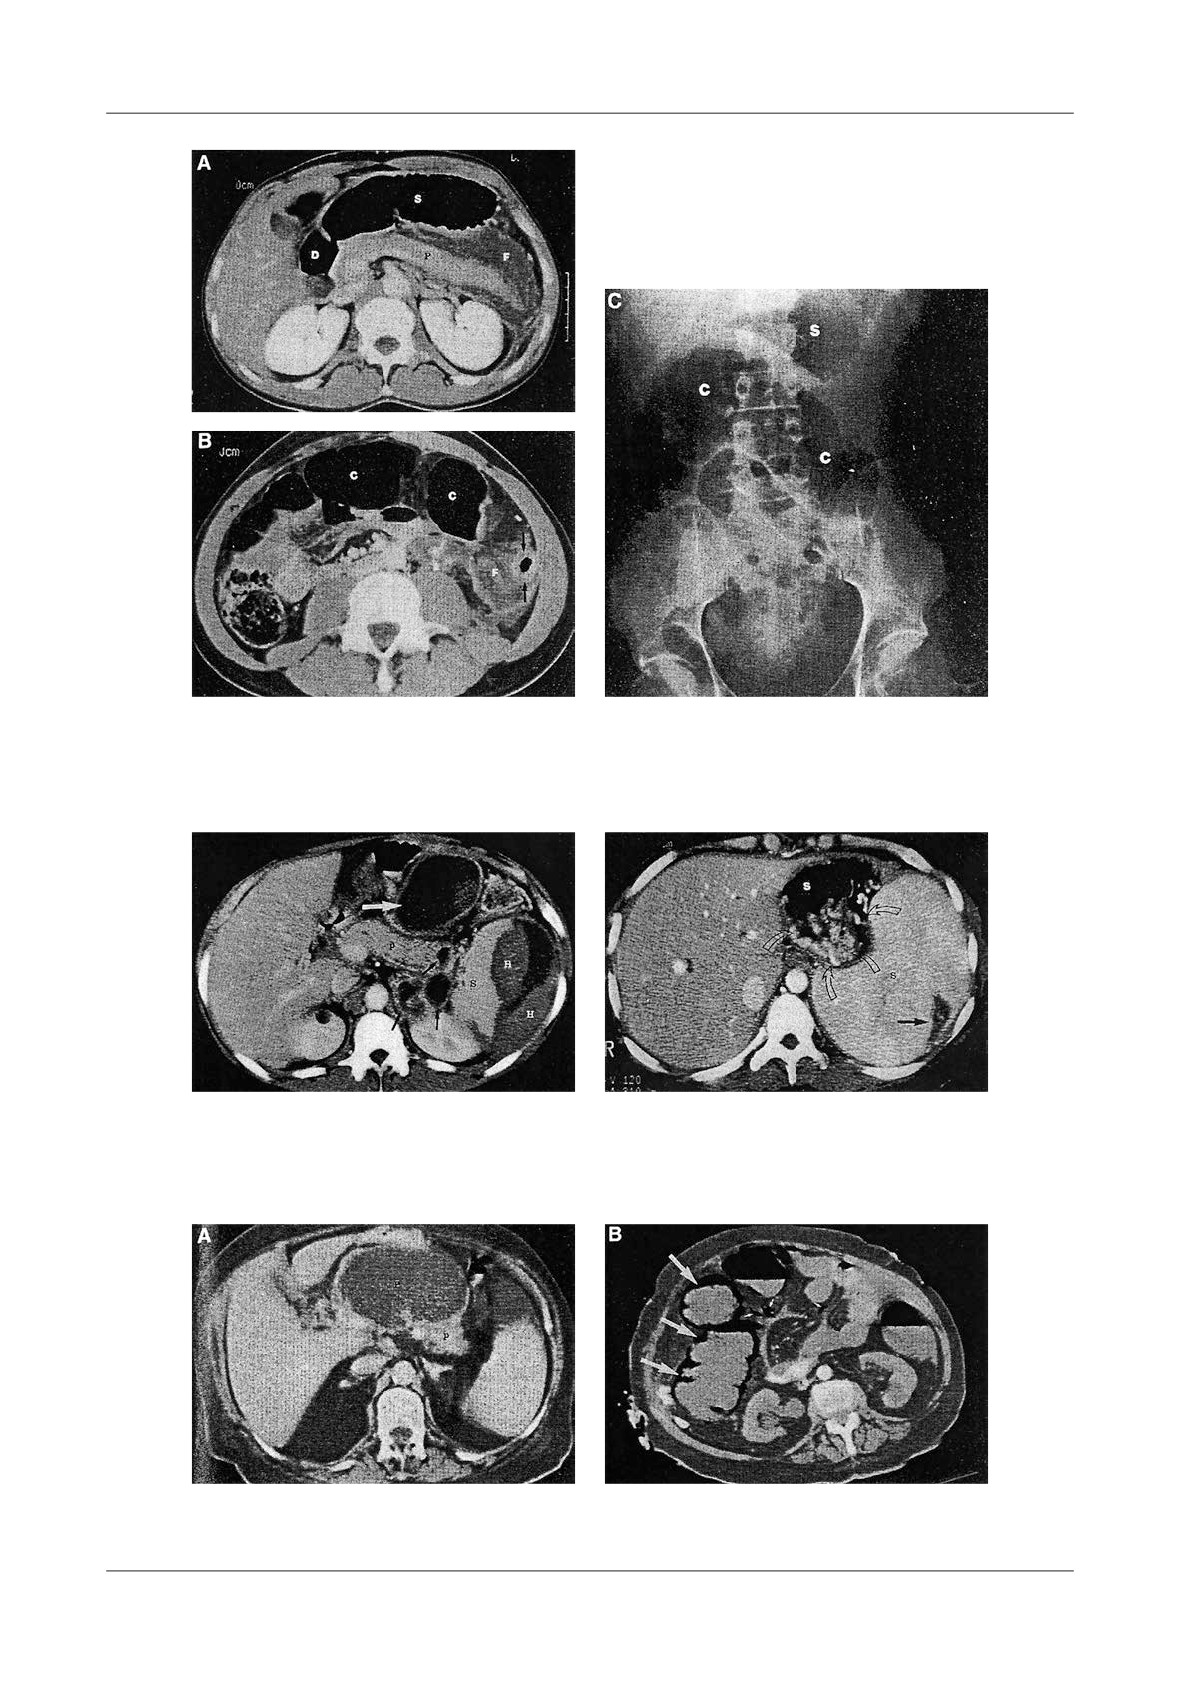

Figure 1. Pancreatic necrosis with the development of a pseudocyst, ileus and colonic in ltration in a 38

-year-old man. A-At admission the CT- shows enlarged pancreas and peripancreatic in ammation,  uid

(N=necrosis, P=pancreas, S=stomach), B-Lique ed necrosis nine days later with partially encapsulated

uid collection in the lesser sac, C-Dilated small bowel loops, with a haustral transverse colon. S=small

bowel, T=transverse colon, D-Five weeks later, fully encapsulated pseudocyst in the lower sac, with

lique ed necrosis in the neck of the pancreas (D=duodenum, N=necrosis, P=pseudocyst, S=stomach)

necrotic tissue (Figure 1).

Figure 2. Infected pancreatic necrosis, more of 50% of the

onset (Fig. 2).

CT image is necrosis, with encapsulated liquefaction

According to our experience the detection of gas in

and air bubbles

the necrotic tissue was present in 12% of cases (Figure

2). Such CT  ndings are indicative of infected necrosis.

e pancreatic abscess occurred in 3 patients (Figure

3), usually

3 to

4 weeks after the onset of acute

pancreatitis.

Figure 4. Pancreatic pseudocyst secondary to necrosis.

A - Liquefaction necrosis in the tail, B - Large pseudocyst bulging into the stomach

Figure 5. Pseudocyst communicating with  the pancreatic duct, A-With CT image of enlarged gland

and peripancreatitis, B-After discharge from hospital, 2 weeks later, CT shows a residual collection,

C-6 months later, the patient had abdominal pain, CT shows an enlarging pseudocyst,

D-Trans gastric punction with  stulography, shows communication with the Wirsung duct

Figure 6. A - Normally enhancing pancreas with peripancreatic  uid collections (D=duodenum,

S=stomach, F= uid, P=pancreas), B - Transverse colon is air  lled and distended, C - Native

abdominal  lm showing distension of transverse colon

Figure 7. Intrasplenic and subcapsular

Figure 8. Splenomegaly and gastric varices with

hemorrhage (H=hemorrhage, S=spleen,

two episodes of pancreatitis. Massive enlarged

P=pancreas)

spleen, with peripheral infarct

Figure 9. Infarcted right colon in A.P. A-CT image shows pseudocyst with pancreatic necrosis

6 weeks following AP, B-One month later CT showed late pneumocystosis